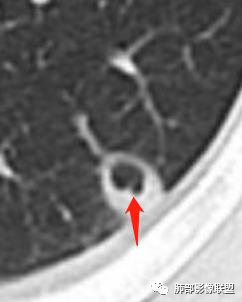

这个图就是理由

尘缘:

@赵永兵 内蒙巴市临河妇幼影像科 支气管是从旁边经过,所以不是空洞,是胸膜下的脓毒栓。如果是结核空洞,应该与支气管相通(因为结核没有血播感染表现的时候,来源是气道,空洞应该与支气管相通),所以支气管从旁边经过,这病灶又在胸膜下,周围也没有干酪坏死。当然是SPE了。